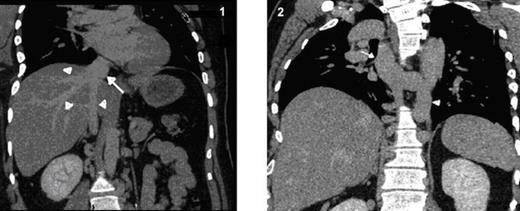

Dilated and tortuous azygous & hemiazygous veins (Fig. 2), with multiple prevertebral and paravertebral collaterals (Fig. 3) as well as superificial collateral veins in the abdominal wall (Fig. 4) were seen. Left renal vein is draining into the hypoplastic segment of IVC (Fig. 5).

Coronal MPR CT image shows grossly dilated azygous vein (arrow) and hemiazygous vein (arrow heads)